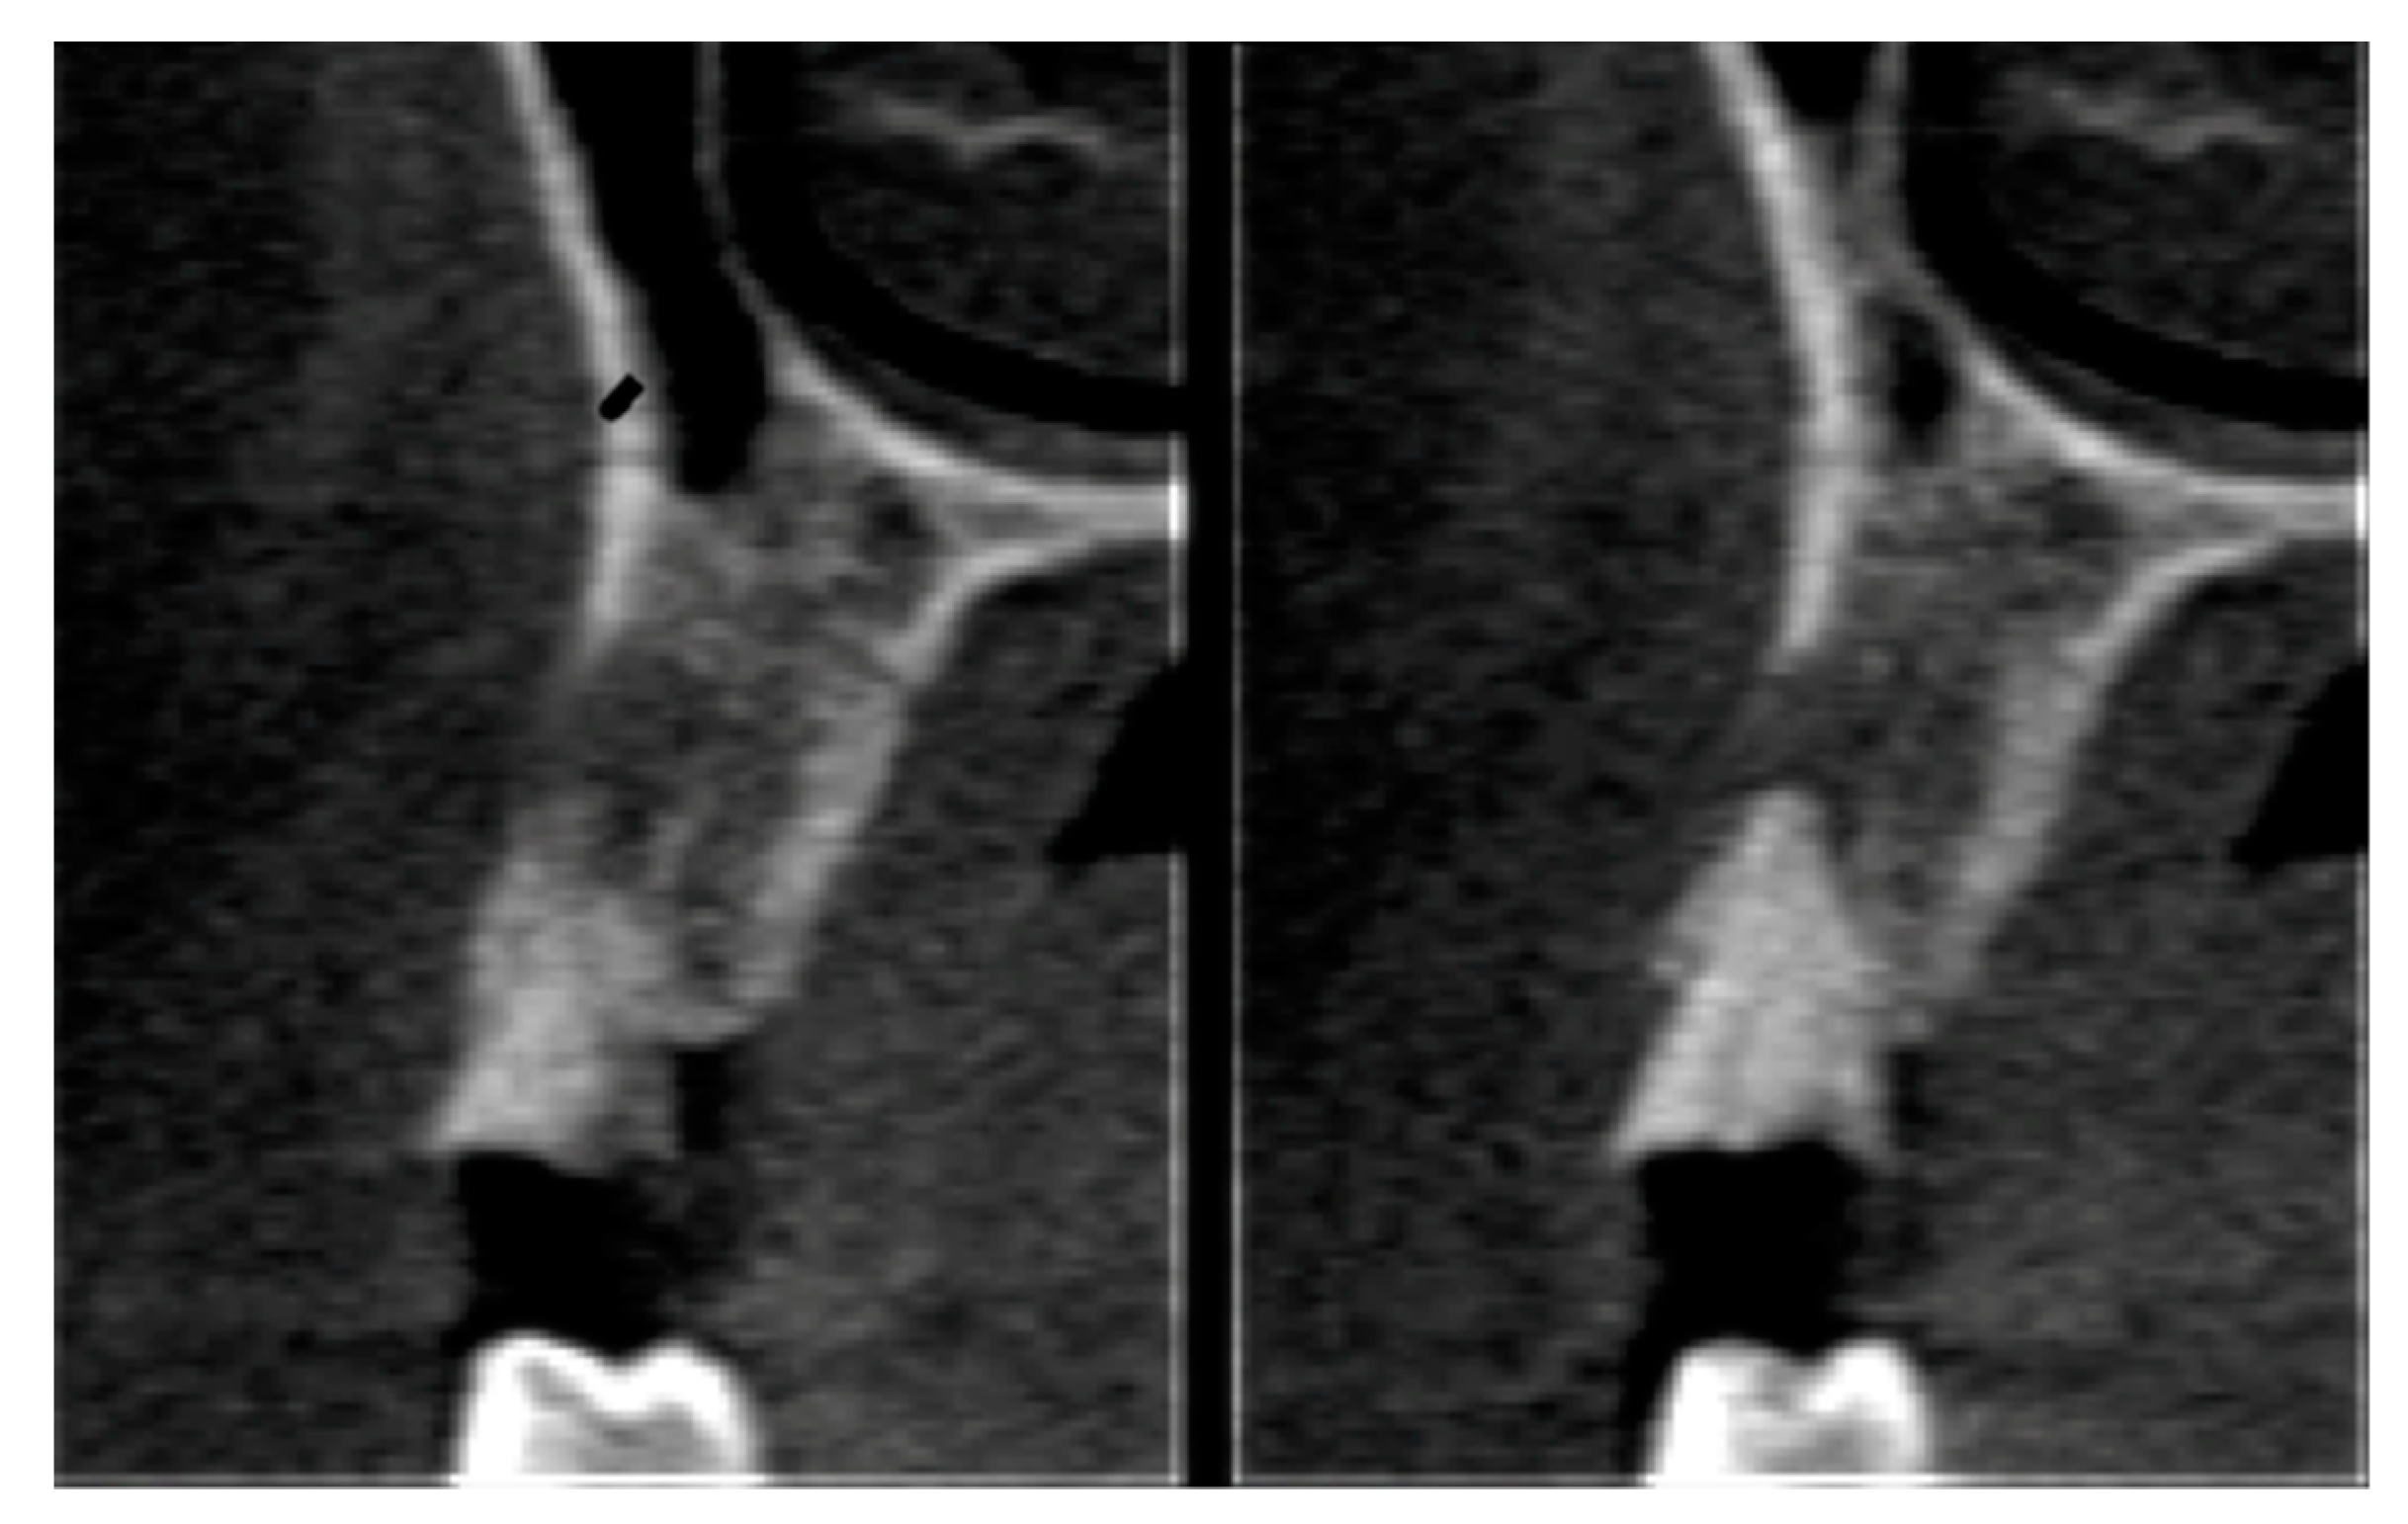

2.6. Tomographic Analysis